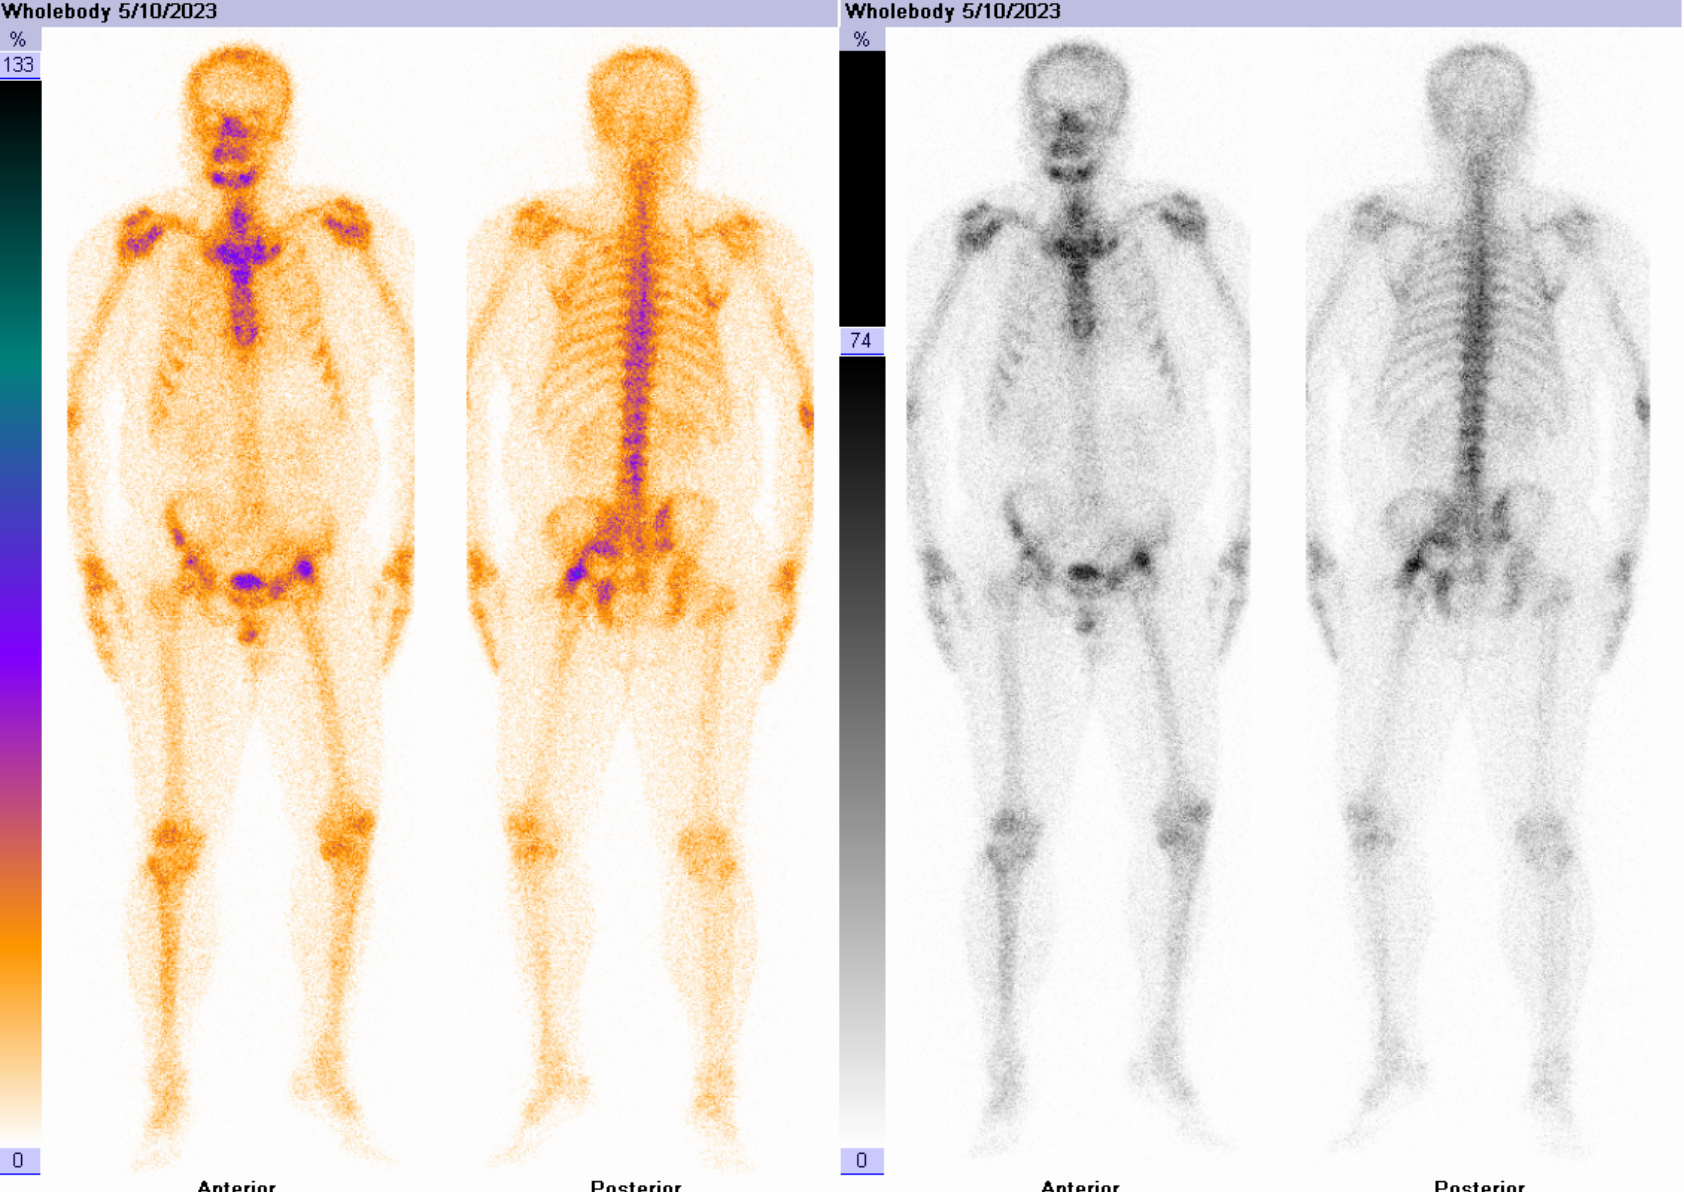

男性患者,13年因“左髋关节术后”于外院行“左侧全髋关节假体翻修”手术治疗,术后康复良好,4年前出现左侧髋关节疼痛,未诊治,3年前左髋关节切口出现窦道、渗液,未治疗。近期患者自觉症状持续加重,入院后完善相关化验检查,血常规:中性粒细胞计数8.53 ↑*10^9/L、C反应蛋白及血沉未见明显异常。

三相骨显像结果提示:左侧髋关节置换术后,三相骨显像示血流及血池相弱阳性,延迟相阳性,结合影像特征不除外假体松动伴局部感染可能。

患者后续行手术治疗,术中发现探查见髋臼及股骨假体已松动,周围见脓汁浸润。